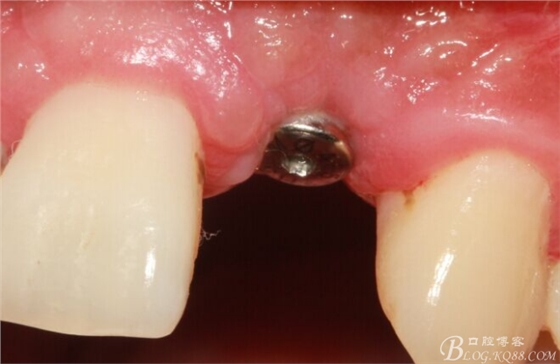

取出影響種植入路的長鈦釘。

擴(kuò)孔。

骨擠壓。

植入植體。